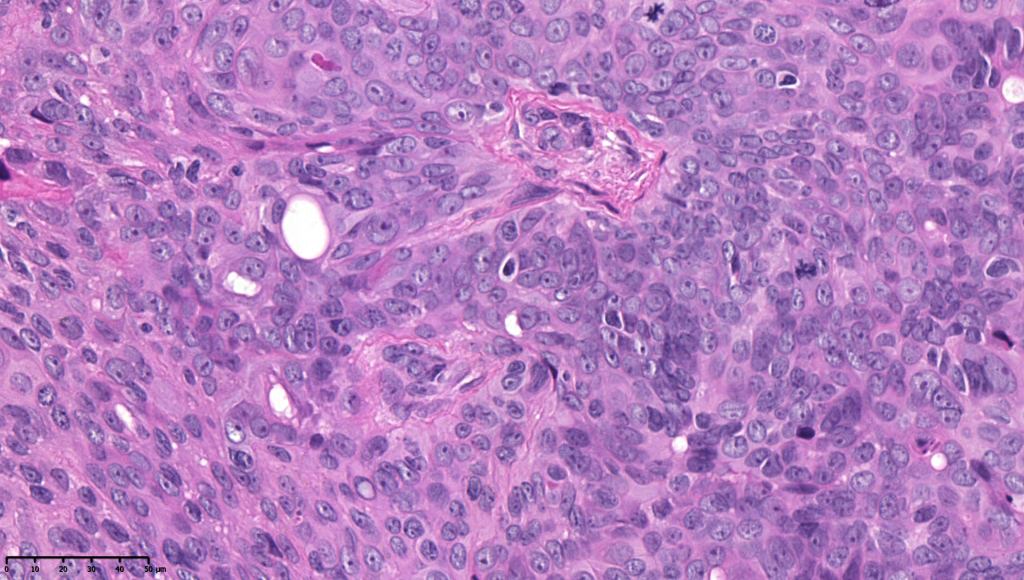

•In poroma, a dermal-centric tumor is associated with epidermal origin/continuity & is composed of small cells with vesical nuclei.

•Desmosomes often prominent

•Clear cells (sometimes predominating- so-called clear cell variant)

•No peripheral palisading or retraction artifact

•Generally few mitoses but occasionally can be conspicuous. In the absence of other features of porocarcinoma, this should not be taken as necessarily implying maligant potential unless other worrying features sre also present (see case below)

•No pleomorphism or abnormal mitoses

•Variable squamous differentiation (can be marked)